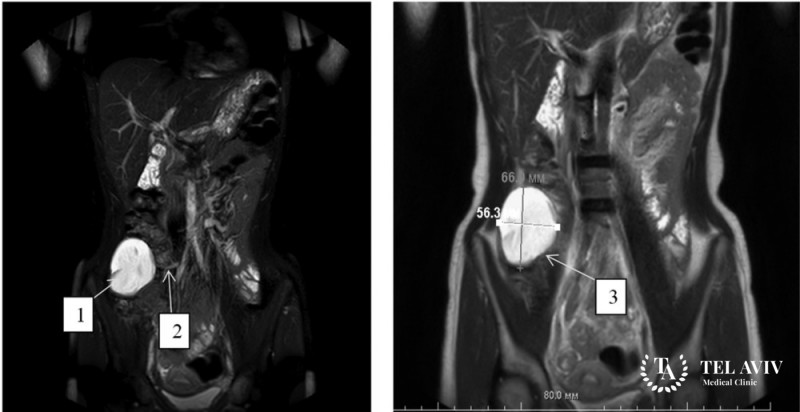

- МРТ или КТ внутренних органов.